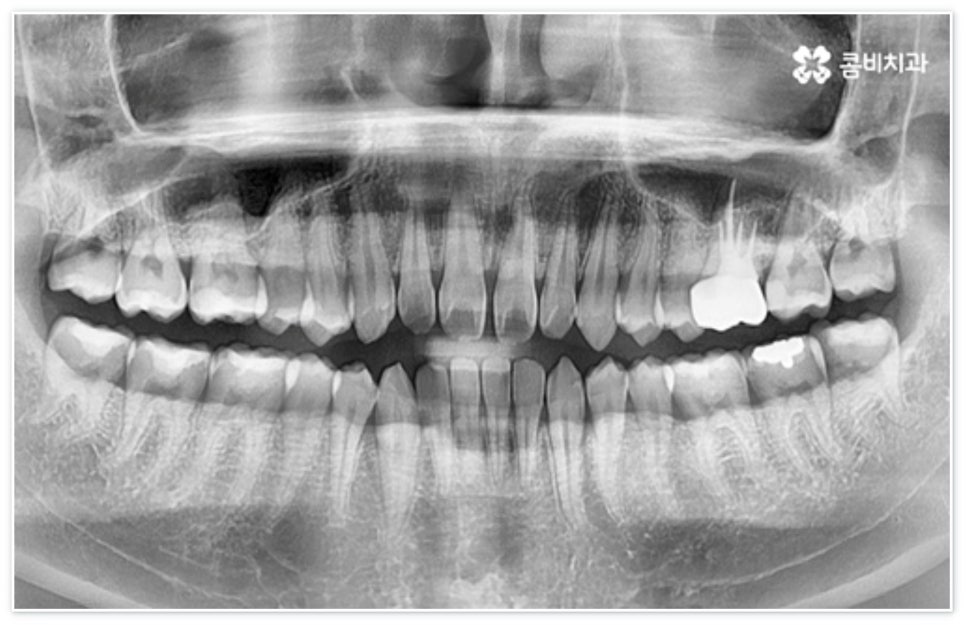

환자분들에 따라 다르지만 통상적으로 전체 교정이 1년에서 2년 반 정도 소요된다면 부분 교정은 6~8개월 정도로 기간 단축이 가능하여 치료에 대한 부담을 줄일 수 있으며 대부분 발치 과정 없이 필요한 부위에만 브라켓을 부착하는 만큼 불편함이 적고 구강 관리도 용이한 편이니 (사진에서 살펴볼 수 있는 케이스) 이에 대해서 자세히 알아보시면 좋을 거예요. 물론 누구나 가능한 것은 아니고 개인의 구강 상태에 따라 진행을 해야 하므로 꼼꼼한 검진과 충분한 상담부터 받아보시길 권유드리고 있습니다.

지금까지 살펴 본 앞니벌어짐 의 원인은 과연 무엇일까요? 먼저 유전적인 원인을 살펴보면 악궁은 큰데 치아가 작을 경우 (왜소치) 치아 사이가 벌어질 수 있고 그밖에도 선천적으로 영구치가 없는 경우, 상대적으로 혀가 비대한 경우 등에도 앞니 사이가 벌어질 수 있어요. 후천적인 원인으로는 치아가 빠진 후 오랫동안 방치하여 서서히 빈 공간으로 치아가 이동하는 것, 치주 질환을 오래 앓아 잇몸이 약해지거나 노화로 인해 잇몸의 탄력이 떨어져서 치아가 한쪽으로 쓰러지거나 치열이 흩뜨러지는 것, 잘못된 생활 습관 (손가락 빨기, 이 악물기, 이 갈이, 혀 내밀기 등) 을 갖고 있는 것 등을 들 수 있습니다.